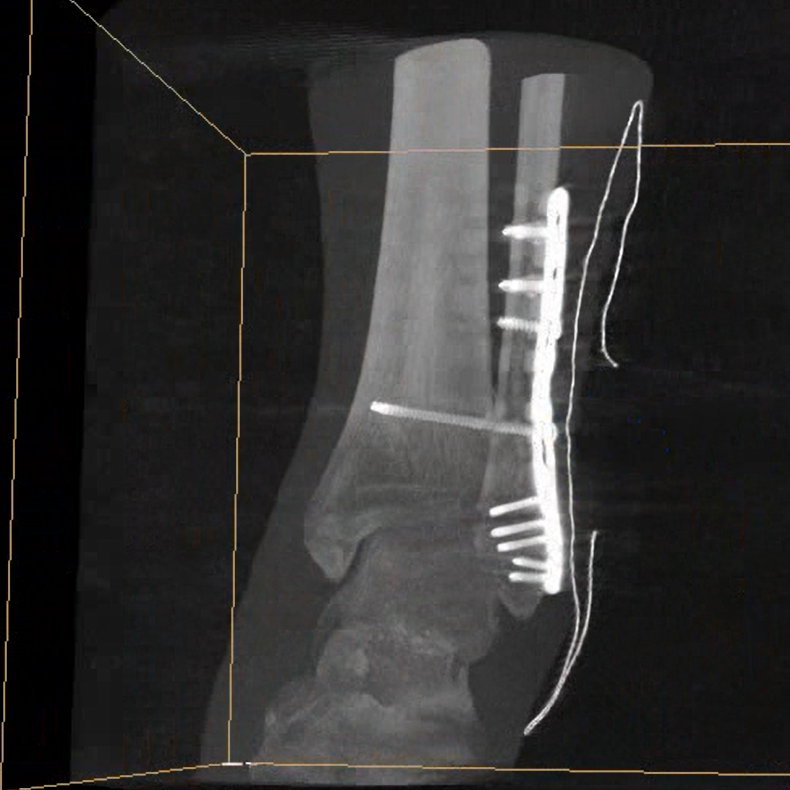

術(shù)中三維成像和橫斷面圖像提供多角度的手術(shù)診斷信息,輔助醫生進(jìn)行術(shù)中評估判斷,諸如骨折復位情況和內植入螺釘的尺寸和位置,輔助手術(shù)更好地完成。

平板垂直升降運動(dòng) 便于術(shù)中微調平板與拍攝主體的距離,更加貼近病灶體,成像范圍更大,圖像更清晰。